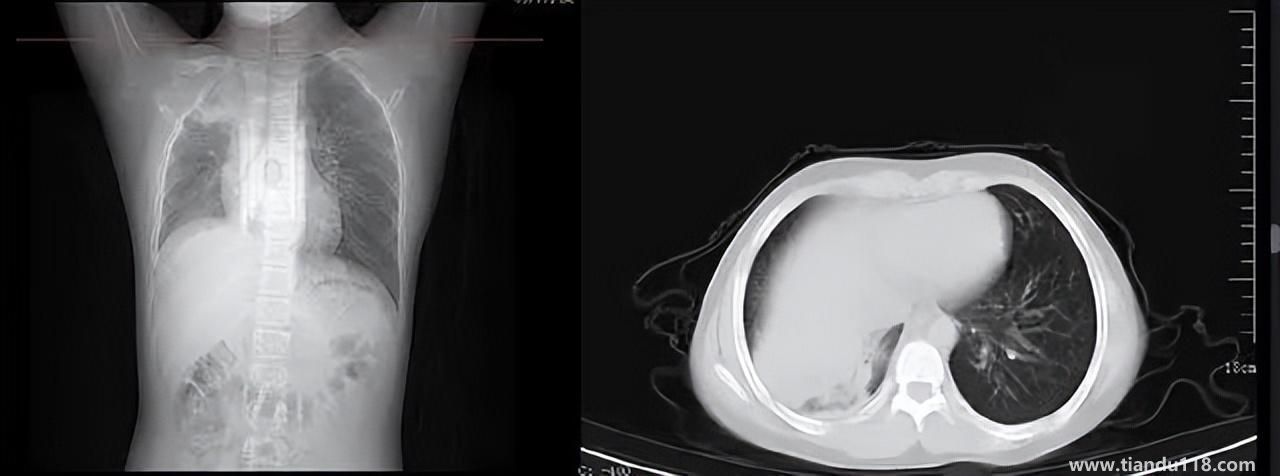

3個(gè)辦法可提前預(yù)警白肺(咋預(yù)防“白肺”) 3個(gè)辦法可提前預(yù)警白肺(咋預(yù)防“白肺”)家里有老人,擔(dān)心出現(xiàn)“大白肺”、“沉默型缺氧”等情況,具體如何應(yīng)對(duì),提前預(yù)警?近日,大象新聞接到諸多咨詢。針對(duì)這些問(wèn)題,大象新聞?dòng)浾咦隽硕喾讲稍L。什么是白肺?對(duì)... 小編 2022-12-28 717

男孩咳嗽發(fā)熱在家硬扛成白肺(醫(yī)生表示以下幾種情況別硬“扛”) 男孩咳嗽發(fā)熱在家硬扛成白肺(醫(yī)生表示以下幾種情況別硬“扛”) 近日,一名12歲男孩咳嗽一周不就醫(yī),一側(cè)肺部“扛”成了“白肺”。“抱著僥幸心理一直在家硬‘扛’,沒(méi)想到‘扛’出這么重的病!”孩子家長(zhǎng)悔不... 小編 2022-12-28 967

為何有人出現(xiàn)“白肺”?專家回應(yīng)和疫苗接種無(wú)關(guān) 為何有人出現(xiàn)“白肺”?專家回應(yīng)和疫苗接種無(wú)關(guān)國(guó)務(wù)院聯(lián)防聯(lián)控機(jī)制12月27日召開新聞發(fā)布會(huì),針對(duì)有媒體提問(wèn)稱,從近期公眾的反映情況看,有的新冠病毒感染者在就診過(guò)程中發(fā)現(xiàn)了肺炎或者是CT出現(xiàn)了“白肺”的現(xiàn)... 小編 2022-12-27 841

感染新冠會(huì)變白肺?醫(yī)生:有年輕病例 感染新冠會(huì)變白肺?醫(yī)生:有年輕病例感染新冠會(huì)變白肺嗎?對(duì)此,有專家表示,造成“白肺”情況有很多種,感染新冠只是一種可能。少量患者肺有滲液 ,咳嗽不會(huì)引發(fā)白肺,有年輕人病例。... 小編 2022-12-27 629